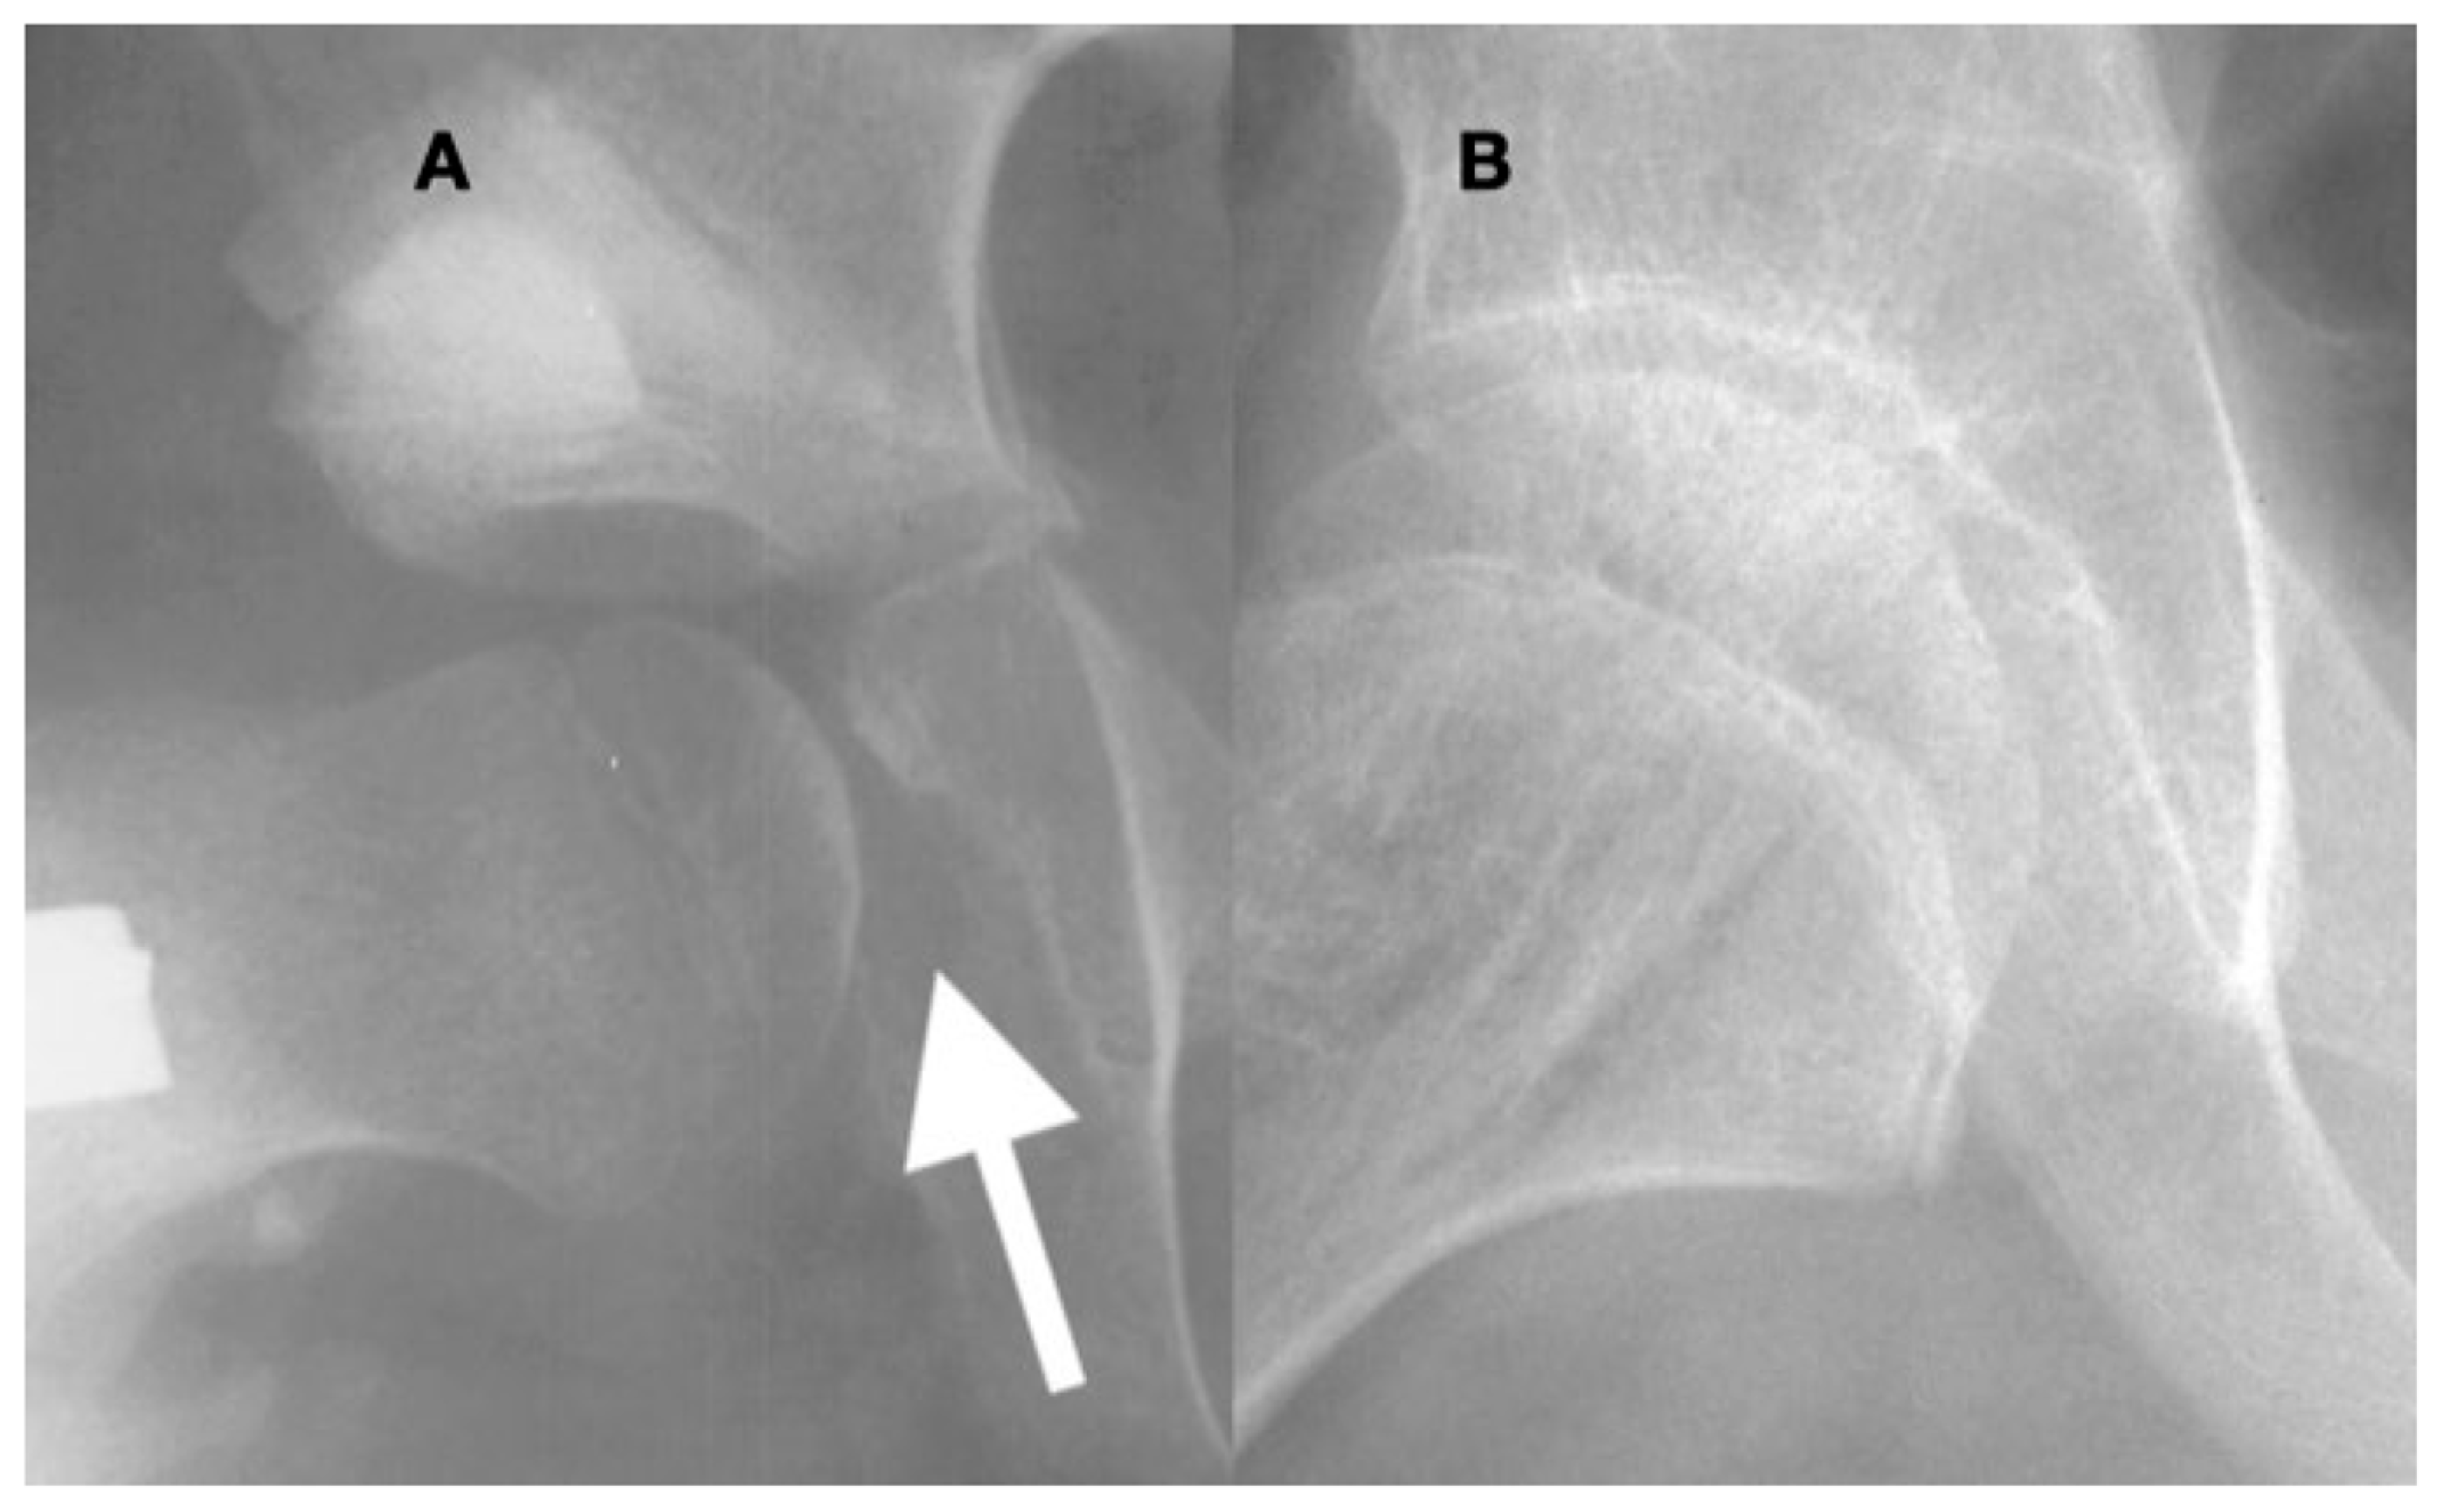

3.4. Femoral Factors Influencing Hip Pathology

3.4.1. Pathologic Role of Femoral Anteversion

3.4.2. Pathologic Role of Coxa Valga and the Impact of its Correction on Spastic Hips